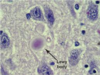

- Balloon neurons on pathology